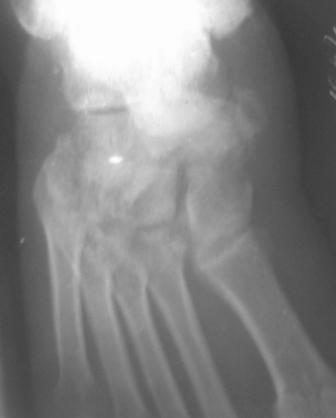

Уважаемый Абдурашид, с большой долей вероятности можно говорить о том, что в результате ДТП пациент плучил вывих в суставе Шопара с переломом одной из костей, скорее всего, действительно ладьевидной. Подтвердить это можно, попытавшись сделать более качественные ргр плюс снимки косым лучом для идентификации передних отделов таранной кости и таранно-ладьевидного сустава. Как я понимаю, выполнить КТ для данного пациента маловероятно. Тогда попробуйте воспользоваться таким старым, но в ряде случаев эффективным методом, как сравнительные Ргр здоровой конечности. Если Вы подтвердите д-з вывиха, а скорее да, по сохраняющемуся подвывиху, да иначе и сложно себе представить, как произошло такое смещение фрагмента, и, учитывая срок с момента травмы, Вам придётся выполнить артродез таранно-ладьевидного и, скорее всего, пяточно-кубовидного сочленений. С уважением, Волна

По данному случаю, оказалось 3 месяца назад было произведена Р-графия в райбольнице, но больной предпочел лечится у табиба. Присылаю первичные снимки.